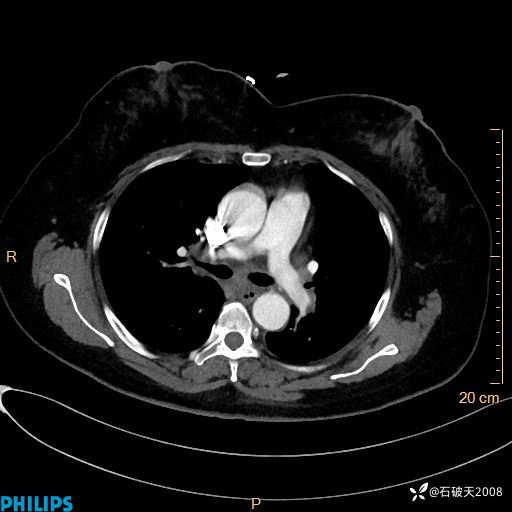

肺结节病?纵膈型肺癌?淋巴瘤?有点意思,欢迎围观

女 52岁 主 诉:咳嗽10余天,咳痰2天。

现病史:10余天前无明显诱因出现咳嗽,呈阵发性干咳,伴咽喉部发痒,无咽痛,无咳痰,无鼻塞、流涕、打喷嚏,无发热、畏寒、寒颤,无头痛、头晕,无胸闷、胸痛,无反酸、烧心,无腹痛、腹泻,无尿频、尿急,无皮疹等,在当地诊所求治,给予口服药物治疗(具体不详),病情无好转。遂在当地社区卫生服务中心开具口服药物治疗(具体不详),疗效欠佳。2天前出现咳痰,在我院门诊求治,行胸部CT提示肺部感染,建议住院,患者要求口服药物治疗,目前仍咳嗽、咳白色粘痰,白天量多,夜间自觉喉部喘鸣音,遂再次来院就诊,以“肺部感染”为诊断收入院。发病以来,神志清,精神可,饮食可,夜间睡眠差,大小便正常,近期体重无明显变化。

静脉期